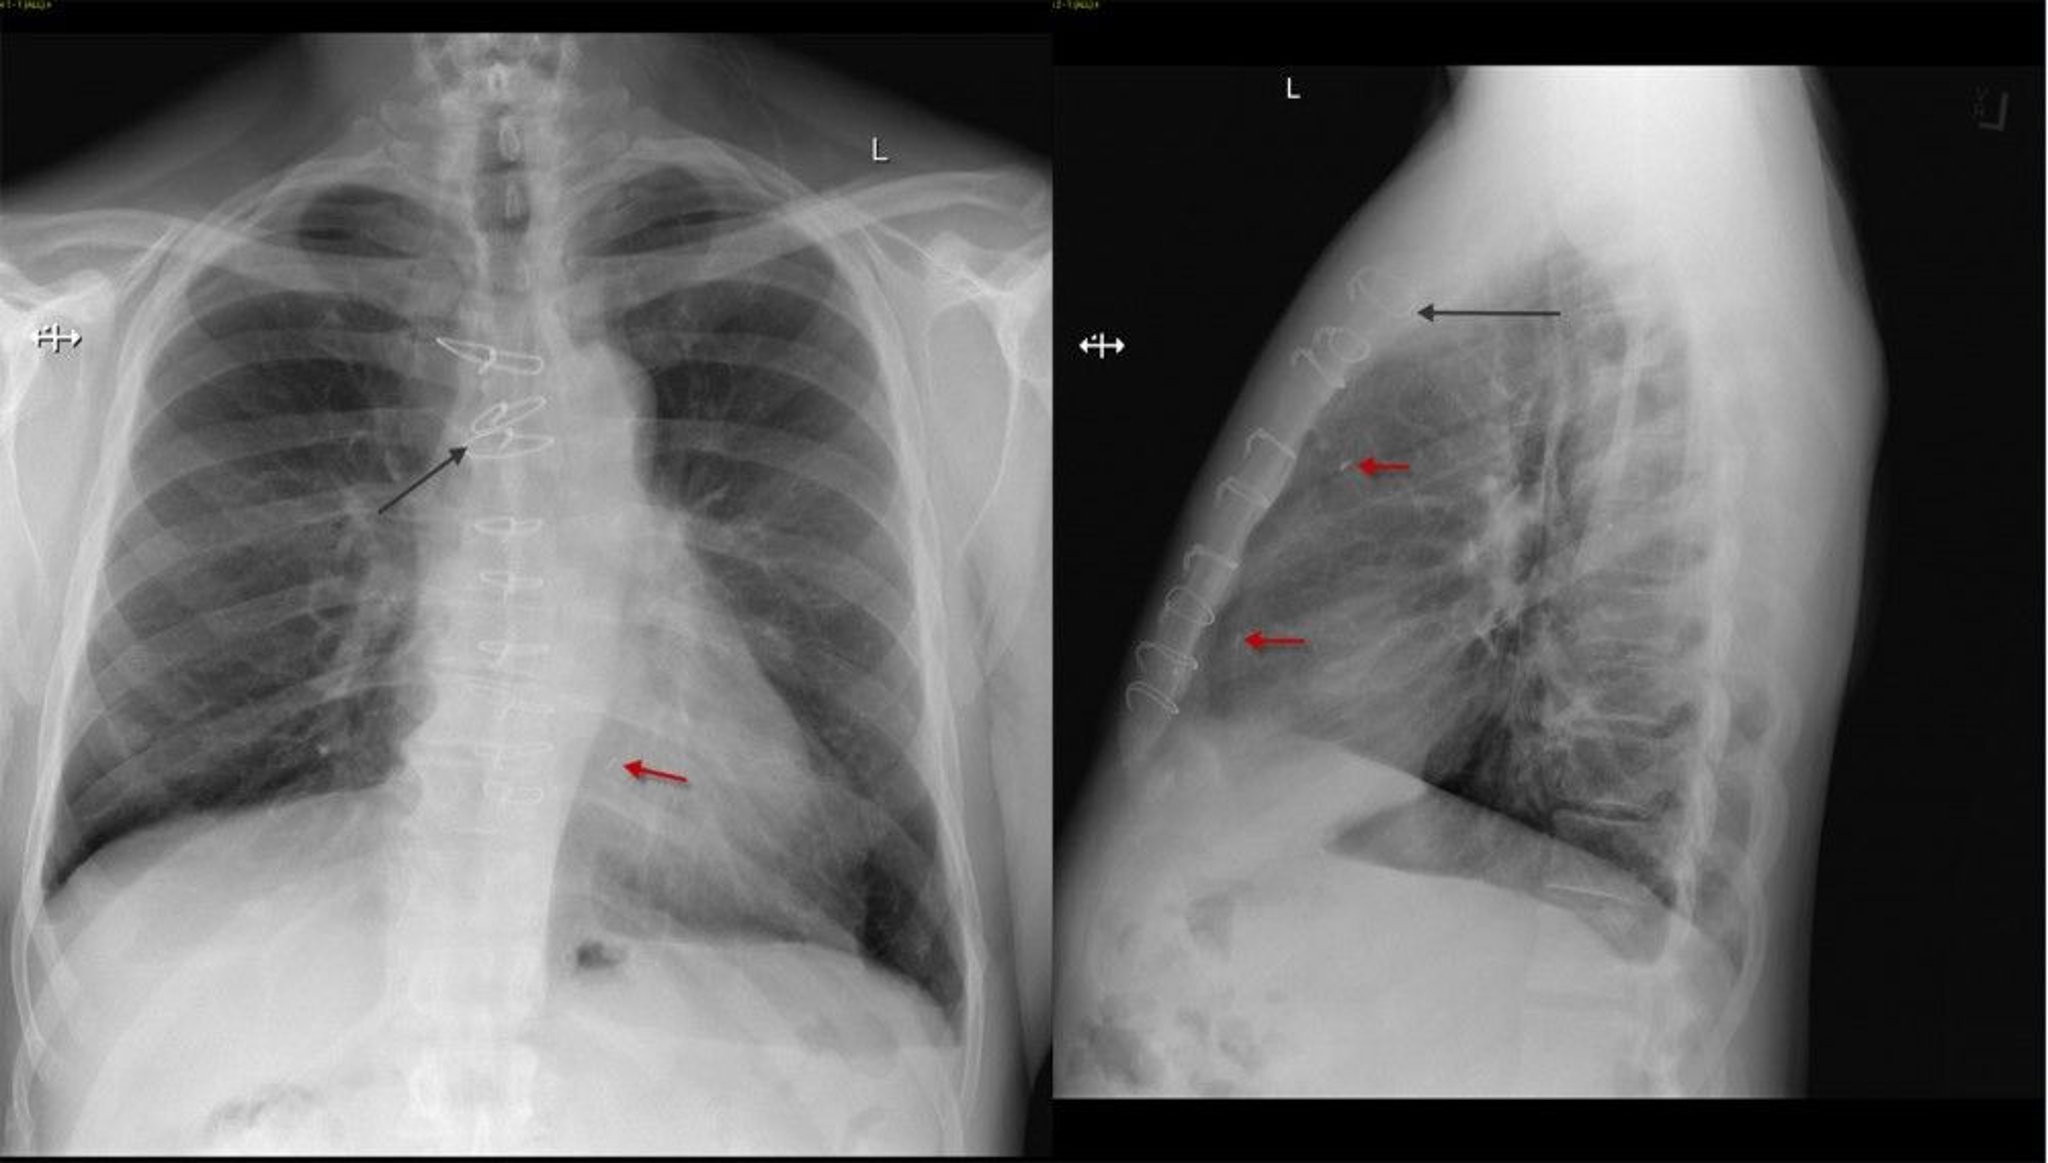

Radiografía de tórax frontal y lateral de un paciente después de una cirugía de derivación de la arteria coronaria que muestra suturas esternales (flecha negra) y clips quirúrgicos (flecha roja).

© 2017 Elliot K. Fishman, MD.